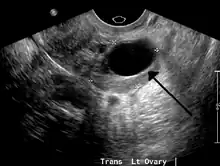

Ultrasound

Follow-up imaging in women of reproductive age for incidentally discovered simple cysts on ultrasound is not needed until 5 cm, as these are usually normal ovarian follicles. Simple cysts 5 to 7 cm in premenopausal females should be followed yearly. Simple cysts larger than 7 cm require further imaging with MRI or surgical assessment. Because they are large, they cannot be reliably assessed by ultrasound alone; it can be difficult to see posterior wall soft tissue nodularity or thickened septation due to limited ultrasound beam penetrance at this size and depth. For the corpus luteum, a dominant ovulating follicle that typically appears as a cyst with circumferentially thickened walls and crenulated inner margins, follow up is not needed if the cyst is less than 3 cm in diameter. In postmenopausal patients, any simple cyst greater than 1 cm but less than 7 cm needs yearly follow-up, while those greater than 7 cm need MRI or surgical evaluation, similar to reproductive age females.[9]

For incidentally discovered dermoids, diagnosed on ultrasound by their pathognomonic echogenic fat, either surgical removal or yearly follow up is indicated, regardless of patient age. For peritoneal inclusion cysts, which have a crumpled tissue-paper appearance and tend to follow the contour of adjacent organs, follow up is based on clinical history. Hydrosalpinx, or fallopian tube dilation, can be mistaken for an ovarian cyst due to its anechoic appearance. Follow-up for this is also based on clinical presentation.[9]

For multiloculate cysts with thin septation less than 3 mm, surgical evaluation is recommended. The presence of multiloculation suggests a neoplasm, although the thin septation implies that the neoplasm is benign. For any thickened septation, nodularity, vascular flow on color doppler, or growth over several ultrasounds, surgical removal may be considered due to concern of cancer.[9]